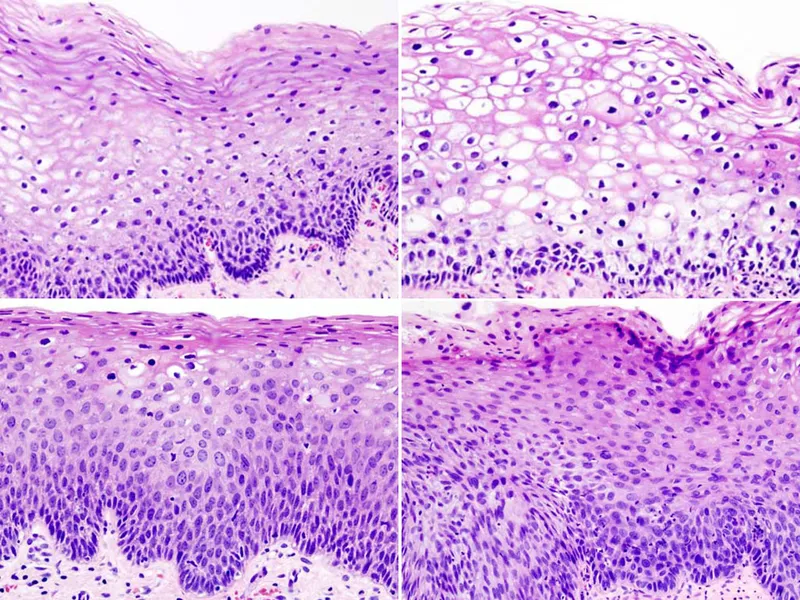

Dysplasia - Disorderly Arrangement

- Definition: Disordered growth and maturation of epithelium; a non-neoplastic, disorderly proliferation.

- Loss of cellular uniformity (pleomorphism) & architectural orientation.

- ↑ Nuclear-to-cytoplasmic (N:C) ratio.

- Nuclear hyperchromasia and clumping.

- Increased and/or atypical mitotic figures.

Progression & Grading - The Slippery Slope

- Dysplasia exists on a spectrum. The risk of progression to invasive carcinoma increases with the grade of dysplasia. It represents a stepwise accumulation of mutations.

- Grading is based on the vertical extent of dysplastic cells within the epithelium.

- Mild (Low-Grade): Involves the basal 1/3 of the epithelium (e.g., Cervical Intraepithelial Neoplasia - CIN 1).

- Moderate (High-Grade): Involves up to 2/3 of the epithelium (e.g., CIN 2).

- Severe (High-Grade): Involves more than 2/3 of the epithelium (CIN 3).

- Carcinoma in Situ (CIS): Full-thickness involvement, but the basement membrane is intact (CIN 3).